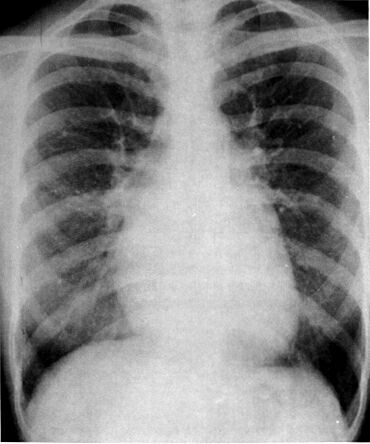

Рентгенограмма больного С.

Митральная конфигурация 1 типа: увеличение левого предсердия и правого желудочка. Признаки легочной гипертензии.